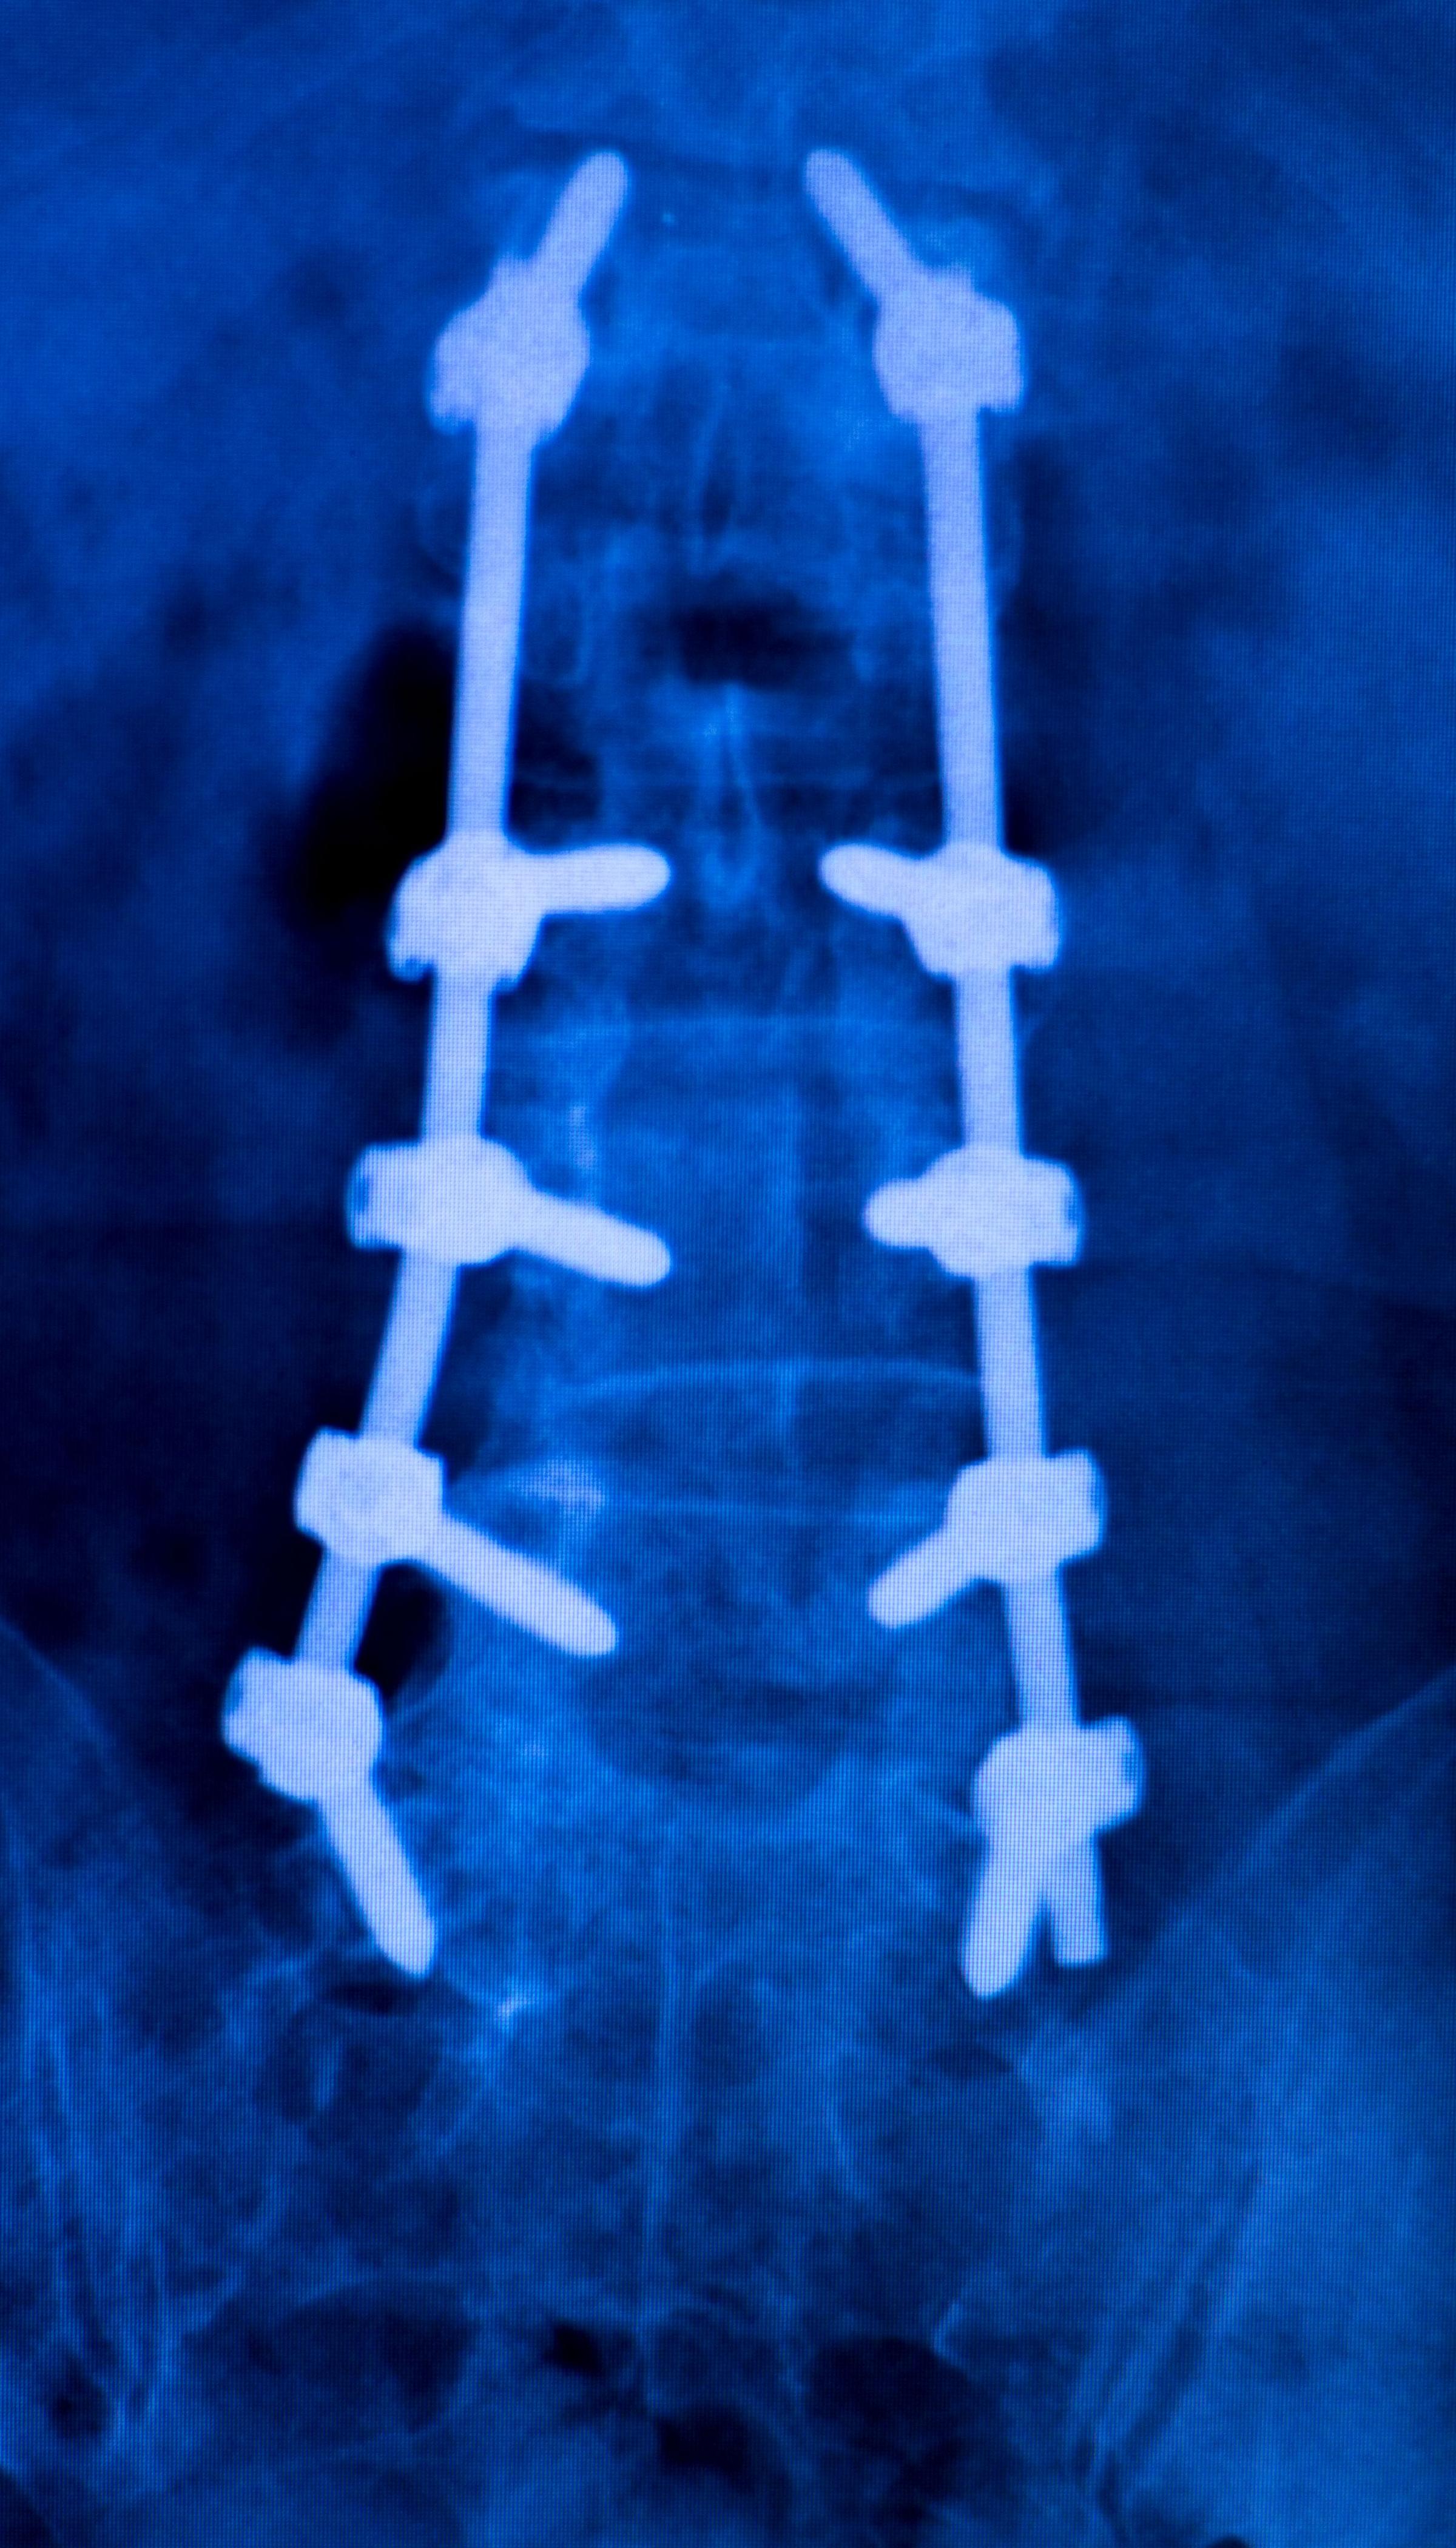

If you have spinal fusion surgery, your doctor may use rods, screws, or cages. These devices hold your bones in place. They help your spine fuse and heal the right way.

Spinal implants help fix problems like scoliosis or kyphosis. These devices keep your spine straight while you heal. Doctors use rods, screws, and hooks to make your spine straight and hold it in place.

Implants keep your spine in the right spot while you heal.

They work with spinal fusion to keep your spine straight for a long time.

For scoliosis, surgery makes your spine straight and uses implants to keep it steady.

For kyphosis, implants help bring back a natural curve and make your spine stable.